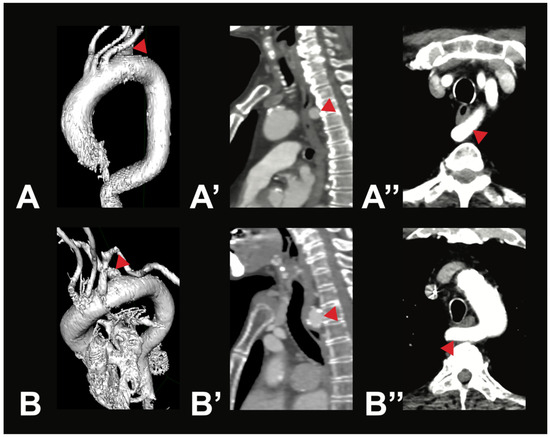

Identifying Aortic Arch Branching Variations Using Advanced Imaging Techniques

Background and Objectives: The branching pattern of the aortic arch (AA) is highly variable, with the typical supra-aortic branching configuration observed in about three out of four cases. Even though some variants carry a heightened risk for certain diseases and intraoperative complications, [...] Read more.

Background and Objectives: The branching pattern of the aortic arch (AA) is highly variable, with the typical supra-aortic branching configuration observed in about three out of four cases. Even though some variants carry a heightened risk for certain diseases and intraoperative complications, they are often underrepresented in standard textbooks. One of the earliest meta-analyses on this topic was published by Dr. Herbert Lippert in 1967. This study aims to use modern imaging to identify AA variations, compare the prevalence with Lippert’s findings, and evaluate the relevance of his classification in today’s Central European population. Materials and Methods: Computed tomography angiography (CTA) scans of 400 patients were retrospectively analyzed and categorized according to Lippert’s classification of AA variations. The prevalence of each variation was calculated and compared to the results reported by Lippert. Results: The typical AA branching was observed in 75.5% of cases. Brachiocephalic trunk variations were the second most common, occurring in 19.5% of patients. Variations involving the left vertebral artery branching directly off the AA had a prevalence of 4%. Additionally, two cases (0.5%) exhibited a thyroidea ima artery originating from the AA, and two cases (0.5%) demonstrated an arteria lusoria with a retroesophageal course. Conclusions: Lippert’s classification remains highly relevant in describing supra-aortic branching pattern prevalence within today’s Central European population. Although most variants are of limited clinical relevance, some can become symptomatic or cause complications during medical interventions. Awareness of these variations is therefore essential for optimal patient care. Full article